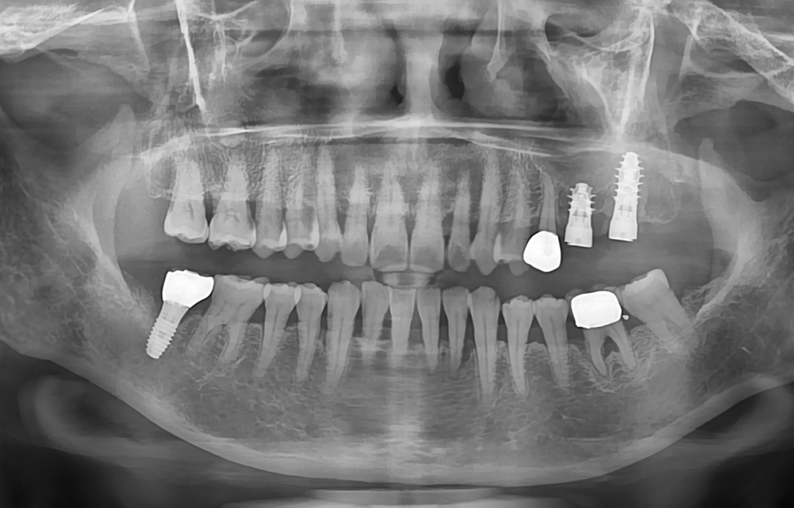

Post-operative panoramic radiograph